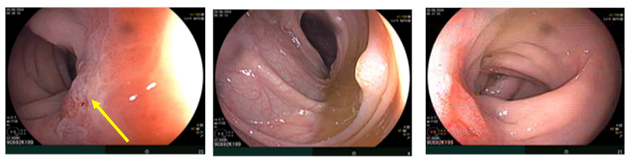

MRI tiểu khung:

Hình 5: Vị trí cạnh đáy tử cung hai bên có các đám ngấm thuốc mạnh, lớn nhất kích thước 18x19mm, ranh giới không rõ với lớp cơ ngoài tử cung và các quai ruột lân cận (mũi tên đỏ). Trực tràng xẹp, hạn chế đánh giá,sơ bộ thấy dày nhẹ thành trước trực tràng cao, dày nhất 7mm, trên đoạn dài 50mm, tăng ngấm thuốc nhẹ sau tiêm, không thấy mất cấu trúc lớp, không thấy thâm nhiễm ngoài thành (mũi tên vàng).

Hình 6: Nhiều dịch tự do ổ bụng, dày nhất do được ở tiểu khung ~35mm (mũi tên đỏ). Dày phúc mạc lan tỏa (mũi tên vàng).